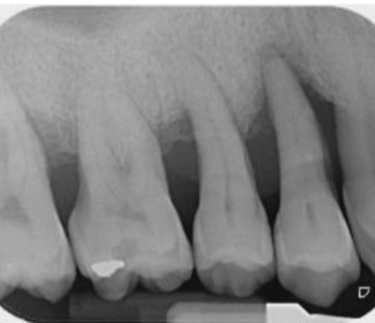

Calcificación Pulpar

La calcificación pulpar es la formación de depósitos de calcio dentro de la pulpa dental, que puede dificultar el tratamiento de conducto.

Los pacientes generalmente no tienen síntomas, pero pueden experimentar sensibilidad.

El tratamiento incluye la eliminación de los depósitos durante el tratamiento de conducto. Es importante tratarlo para evitar complicaciones durante el procedimiento.